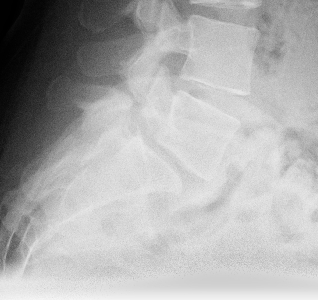

Rechts im Bild ist ein Beispiel einer solchen „sekundären Kyphoskoliose“ bei einem Halb-Wirbel im unteren Brustwirbelsäulenbereich zu sehen. Die operative Korrektur erfolgt durch die Entfernung des Halbwirbels und die Korrektur der Wirbelsäule in allen Ebenen durch ein Schrauben-Stab-System.